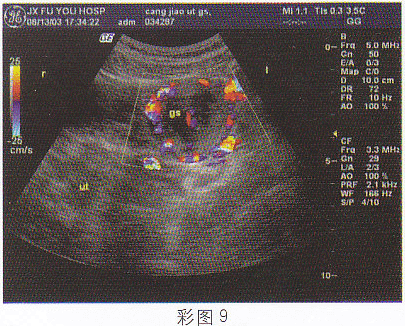

4.女,28岁,停经46天,阴道不规则出血5天,血HCG68μg/ml,结合超声图像,最可能的诊断为(彩图9)![]() |

| 正确答案:D 解题思路:附件区见囊实混合性光团,边界尚清晰,子宫腔内有分离患者有停经,不规则阴道出血,且血HCG增高。 |